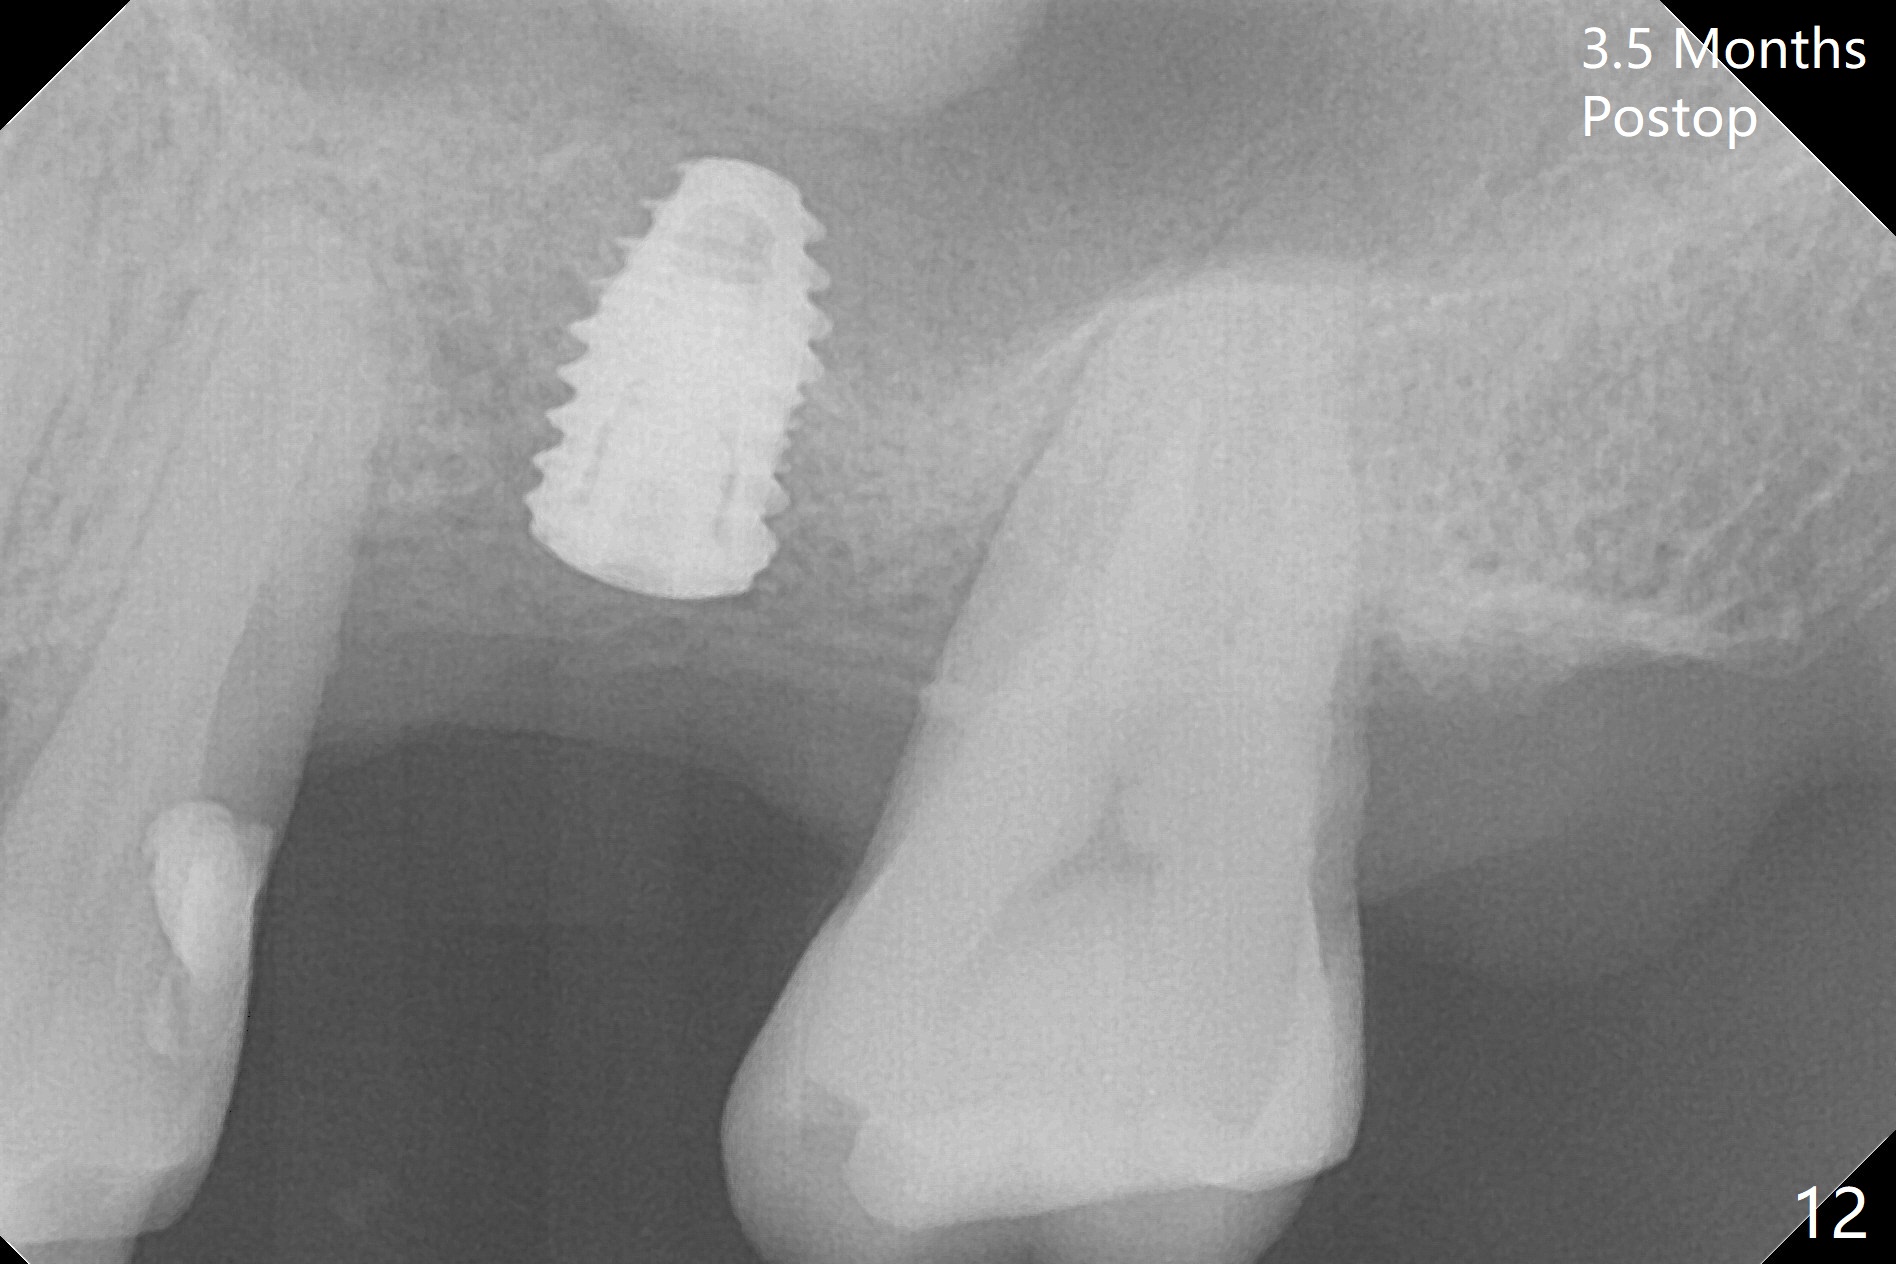

Trajectory of sinus lift without guide at #14 is off (Fig.1 (Magic Sinus Lifter (L) for 9 mm (gingival level)) and needs to be corrected (Fig.2 long line) by re-using 4.8 mm Magic Drill. Following placement of PRF membrane and Demineralized Cortical Allograft (.125-.850 mm) for sinus lift (Fig.3 black dashed line), a 4x10 mm dummy implant is placed with off trajectory. The latter will be fixed by using Lindmann bur to remove the bone distal (Fig.4). The result is less satisfactory with placement of 4.5x10 mm dummy implant (Fig.5). It appears necessary to initiate a new osteotomy (Fig.6 long black line). In fact the result is appealing (Fig.7). The final implant (5x7.3 mm) seems to be placed ideally shown by PA (Fig.8) and BW (Fig.9). Immediately postop CT demonstrates distal defect (Fig.10 *;3-D) and supracrestal placement palatal (Fig.11 P; coronal section). More allograft is then placed in these 2 areas. In all, it is difficult to establish a correct osteotomy without guide. The patient return for uncover 3.5 months postop, although there is a small hole in the middle of the incision (Fig.12). The crown/abutment becomes loose less than 1 month post cementation when the patient chews something tough. It is more related to the unfavorable implant/crown ratio. It is loose again 2 months later. Screw driver is buried inside the abutment with plumber tape. When it is loose for the 3rd time 13 months post cementation, the existing screw driver with a created slot (for retention) is buried without plumber tape after retorque at 35 Ncm (Fig.13). A tissue-level implant should have been used.